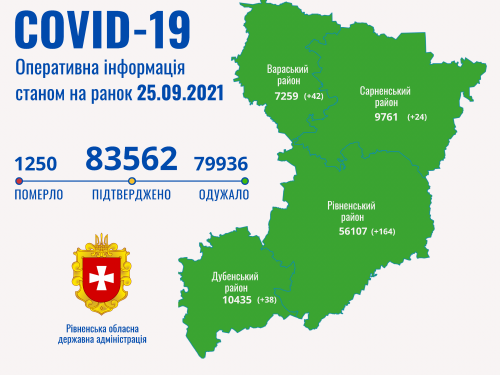

Пів тисячі - у важкому стані, 9 жителів Рівненщини померли за добу від коронавірусу